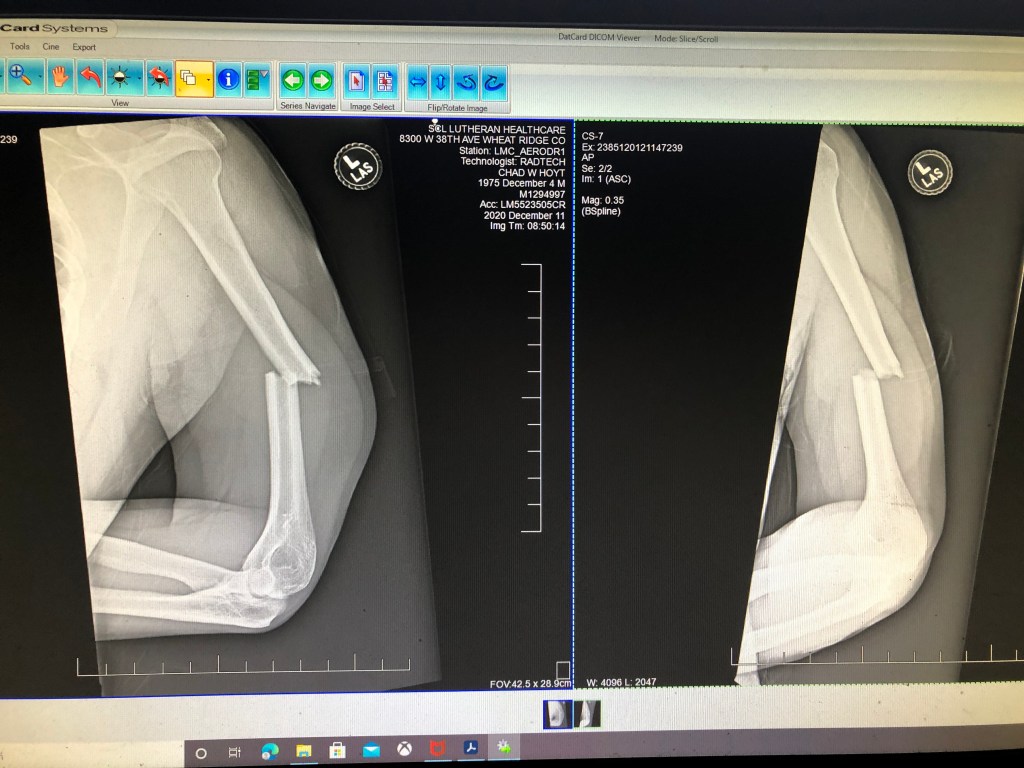

When we got home, I called the orthopedist to make a follow-up appointment. Although the ER’s discharge paperwork said to follow up with ortho in two weeks, it also said it was a displaced, irregular, comminuted, and angulated fracture. Given the radiology report and the odd clicking and dangling sensations Chad was experiencing, I thought it prudent to get him to ortho ASAP. Luckily, they were able to see him the following Monday.

I hadn’t heard anything from the hospital at this point, but Chad called me. He sounded weak and tired but okay. When I got to the hospital, I found out that they had been calling my old land line—they had the wrong number, but no one had bothered to verify it. The surgeon had put a metal rod down the middle of his humerus with two screws at each end to hold it in place. His arm actually looked better after surgery than it had before. The giant lump on the side was gone, and even the swelling in his hand was down.